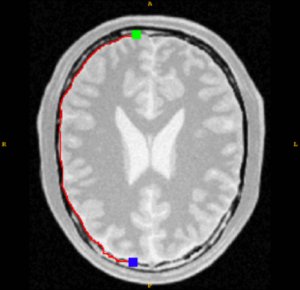

Semi-automatic image segmentation algorithms depend on interaction with the user to accurately define a region of interest within an image. Once such method is a dynamic programming approach called {em Intelligent Scissors} developed by Mortenson and Barret cite{Mortensen1992,Mortensen1995,Barrett1996,Barrett1997}. Standard interaction involves the user-placement of a seed point on or near the boundary of the object to be extracted. Using a gradient-based cost function, a {em live-wire} image path from the seed point to a subsequently placed boundary point is determined. As this free point is manipulated with the mouse cursor, the live-wire boundary, which extends from the seed point to the varying free point, locks onto nearby edges within the image. Although some applications do not require such user-interaction (e.g. cite{Hu2001}) warranting inclusion within the toolkit, incorporating live-wire capabilities into ITK-SNAP cite{Yushkevich2006} has been discussed and, therefore, we would like to, as a preliminary step, vet the code within the ITK community.